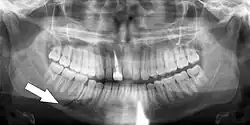

Minimally-displaced fracture in right mandibular. Arrow marks fracture, root canal on central incisor, teeth to the left of fracture do not touch

Panoramic radiograph showing Stafne defect (arrowed).

Dental panoramic radiograph showing dentigerous cyst (arrowed).